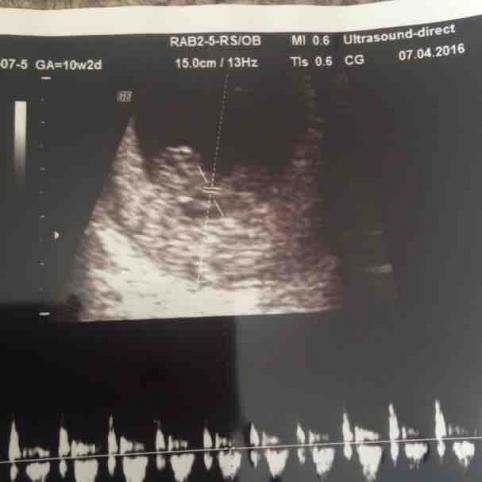

The 10-week ultrasound scan is also called a dating scan , as it is used to determine the gestational age of the baby and predict the due date . The nuchal translucency test is part of this scan . Some parents may choose to get a printed picture of the scan to preserve as a memento .

Ytes I was given my dating scan at 10+2 . I' only 12weeks on Tuesday . You can still get a pretty good pic and I seen the heartbeat fluttering away . We told quite a few after the scan as we had the pic and all was going well . If your scan goes well there's no reason to need a scan at 12weeks . I've now to wait until 22nd Dec for my 20week scan . Good luck . X

Ultrasound in early pregnancy (before 12 weeks ) - Dating Scan Dating ultrasound A 'dating ultrasound' or 'dating scan' is a scan done early in pregnancy (before 12 weeks ) . It is usually done to check how many weeks pregnant you are and therefore to calculate the estimated due date, but it can be done for other reasons . Only a few women need a dating scan .

The dating scan is usually done at some point between 8 weeks and 14 weeks pregnant . NICE recommends it's done between 10 weeks and 13 weeks . You will have had earlier appointments and may have had an early scan if you've had any concerns such as bleeding , but otherwise this is the first time you'll get to see your baby, so it's a real milestone in your pregnancy .